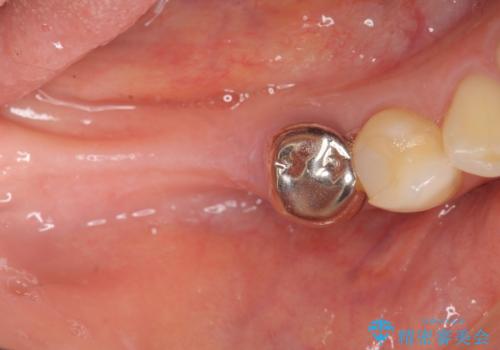

インプラント治療による咬合機能回復

インプラントは高い確率で骨に結合し、しっかりとした咬合力を回復することができます。

長年安心してしっかりと噛んでいただけるよう今回は骨を増成する治療計画としました。